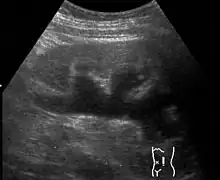

| Renal ultrasonography of hydronephrosis caused by a left ureteral stone | |

Massive hydronephrosis as marked by the arrow- Renal ultrasonography of hydronephrosis[16]

- Stone causing hydronephrosis[16]